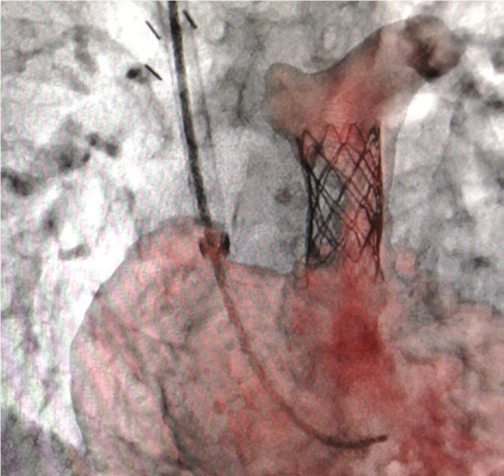

Stent Enhancer* забезпечує візуалізацію стента за рахунок придушення анатомічних структур та фонового шуму.

Stent Mode забезпечує покращену візуалізацію стента в реальному часі без необхідності додаткової окремої обробки або післяобробки.